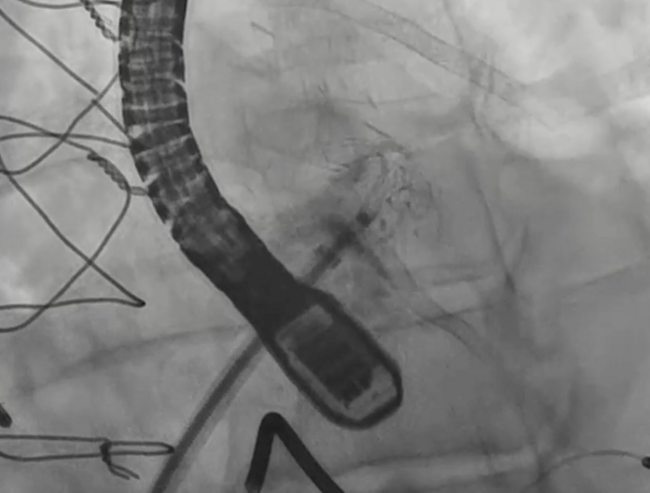

The left atrial appendage (LAA) is a highly variable anatomical structure, which may pose a challenge to successful LAA occlusion with currently approved technology. We present our experience with the compassionate use of the LAmbre LAA closure device. This cine video clip demonstrates the Lambre device after successful implantation and contrast injection in a 79-year-old man with non-valvular atrial fibrillation and multiple falls who was considered high risk for anticoagulation therapy.